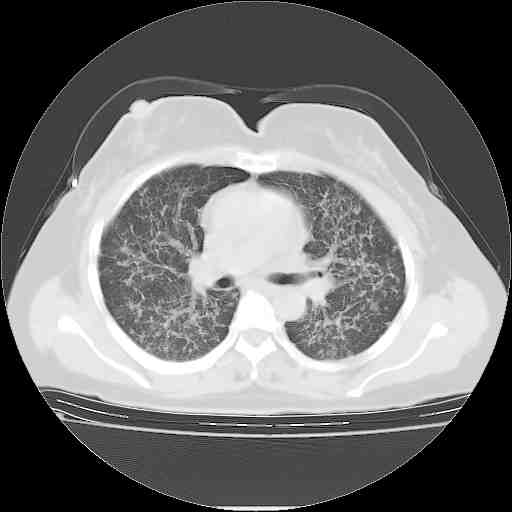

f50,肺ca治疗后,做过穿刺,确诊是肺ca,大家看看这是去年12月做的

考虑  腺癌肺内转移,治疗较前病灶缩小、减少

支持肺癌并肺内淋巴管转移,

肺癌并肺内转移,这种疾病治疗后在影像上看略有好转,不是很显著,但是肿瘤治疗效果影像只是一方面。

支持肺癌并肺内淋巴管炎,  原发灶小了,但转移较前片明显了.

支气管血管束粗而乱,考虑肺癌肺内淋巴管转移,右侧乳房第一二层软组织成份较左侧多,不会有问题吧?

支持右肺下叶周围型肺癌并肺内淋巴管炎,  原发灶小了,但转移较前片明显了.。

标准的细支气管肺泡癌呀!治疗后病情有所控制,也没治愈的迹象!